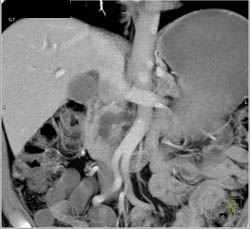

Diagnosis

Intraductal Papillary Mucinous Neoplasm (IPMN)